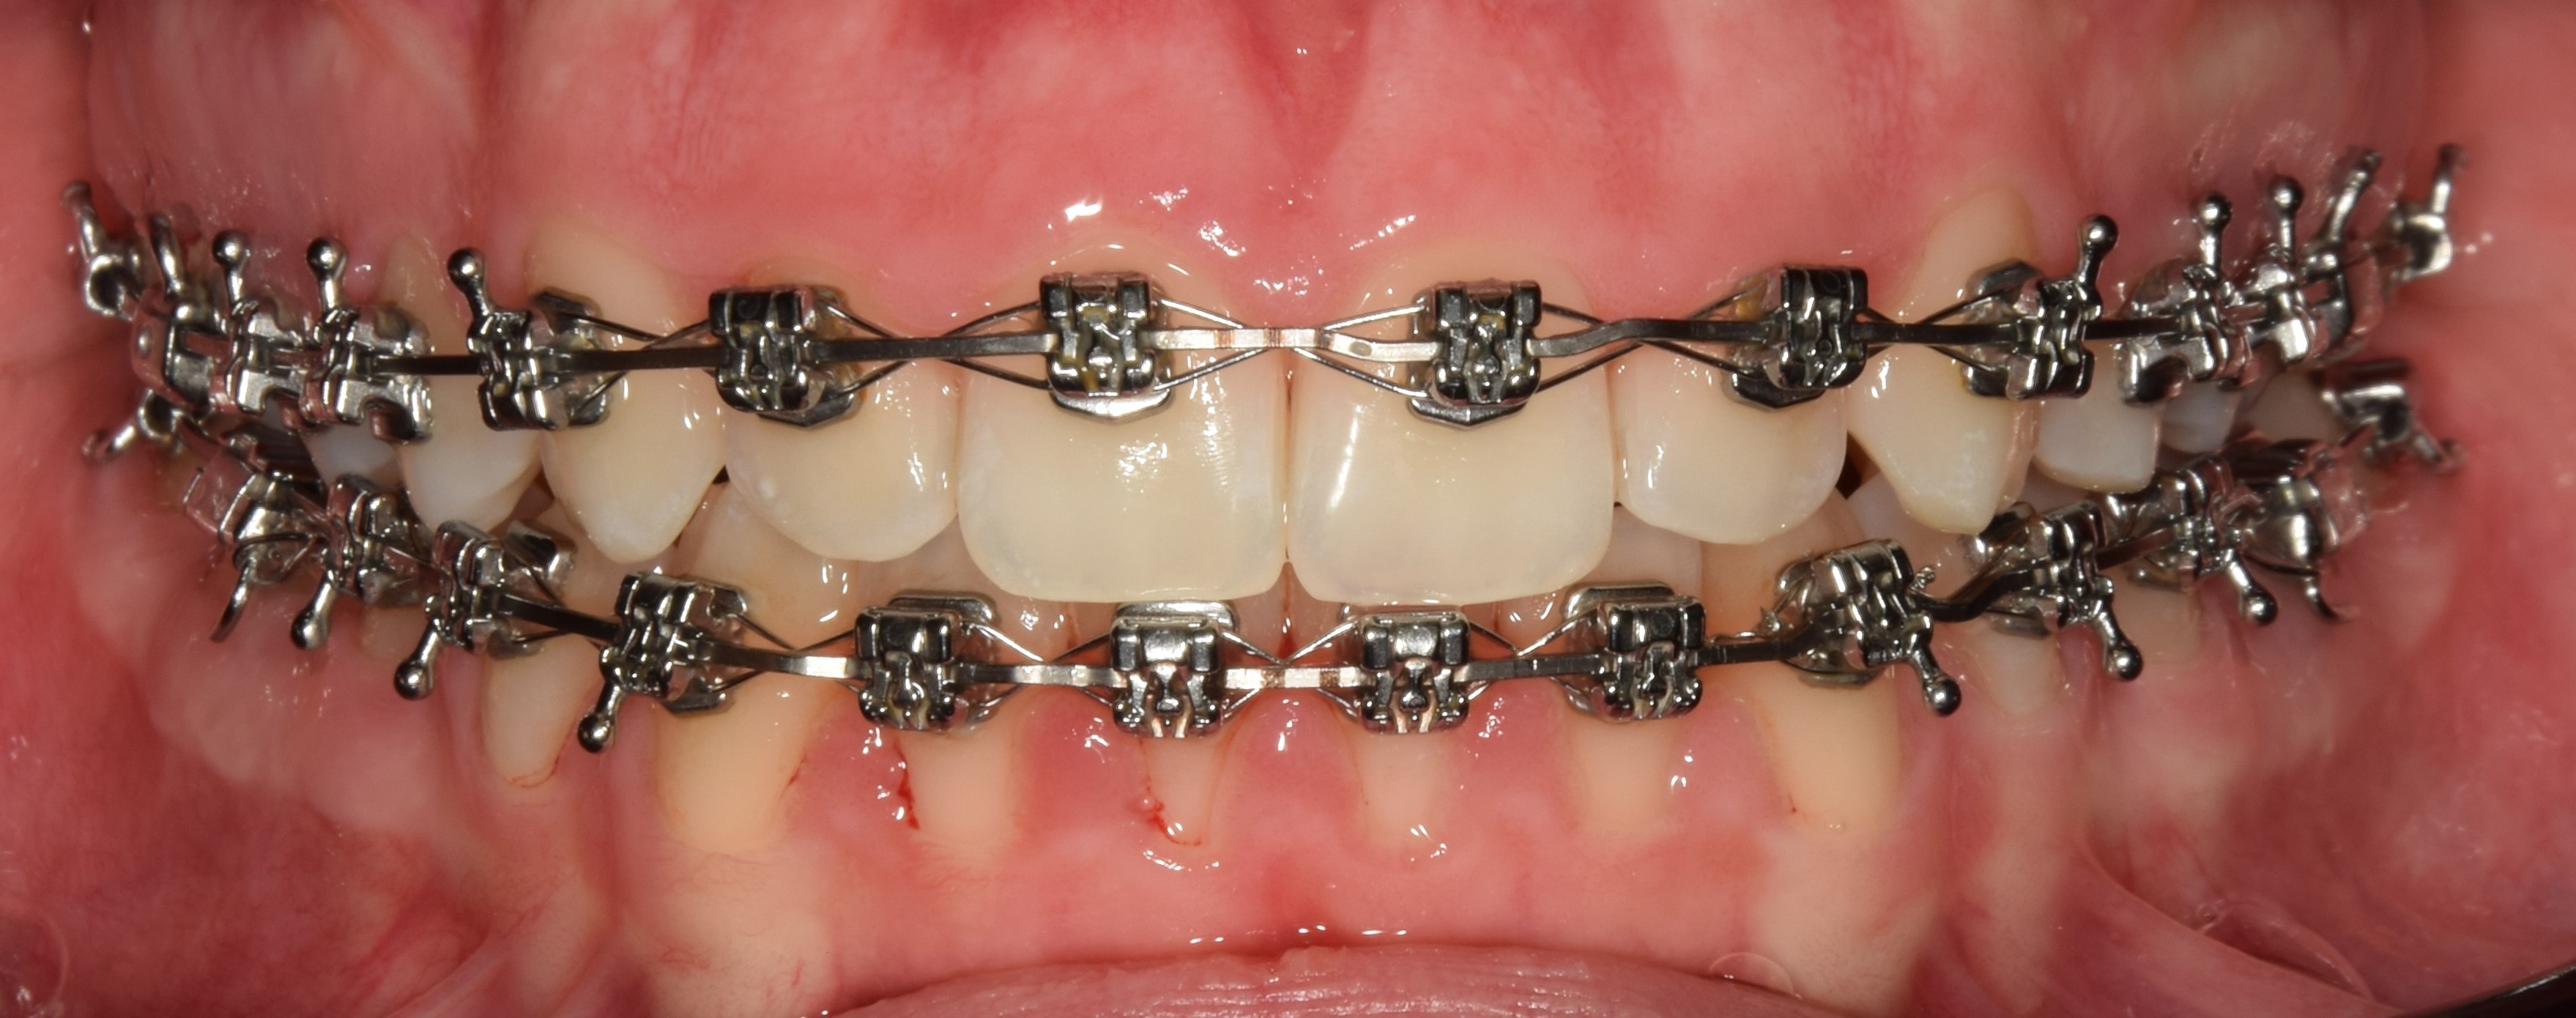

Bracket

Bracketnek nevezzük a rögzített fogszabályzó készülék fogakra ragasztott alkotóelemét, melyekbe a fogszabályzó ívet valamilyen módszerrel rögzítjük. Kisőrlőtől-kisőrlőig dolgozunk bracketekkel, a nagyőrlőkön már tubusok vannak. A bracketek (tappancsok) fogakkal érintkező talpa érdes, hálós szerkezetű, mely jobb rögzülést biztosít. Elsősorban az oldalsó bracketeken (nagyőrlők, kisőrlők, szemfogak), található speciális kampó is. Erre különböző kiegészítő eszközöket akaszthatunk (intermaxilláris gumihúzás, füzérgumi, húzórugó stb.). Anyaga szerint beszélhetünk fém, kerámia, műanyag és arany bracketekről. Az ív rögzítésének típusa szerint megkülönböztetünk hagyományos (az ívet gumival rögzítjük a bracketbe), illetve önligírozó bracketeket (nyitó-záró szerkezettel rögzítjük az ívet).